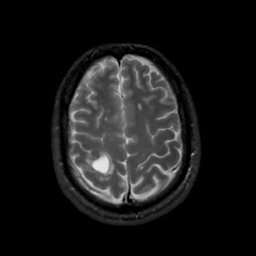

MR Study #7, March 24, 1991 -- Slice #39